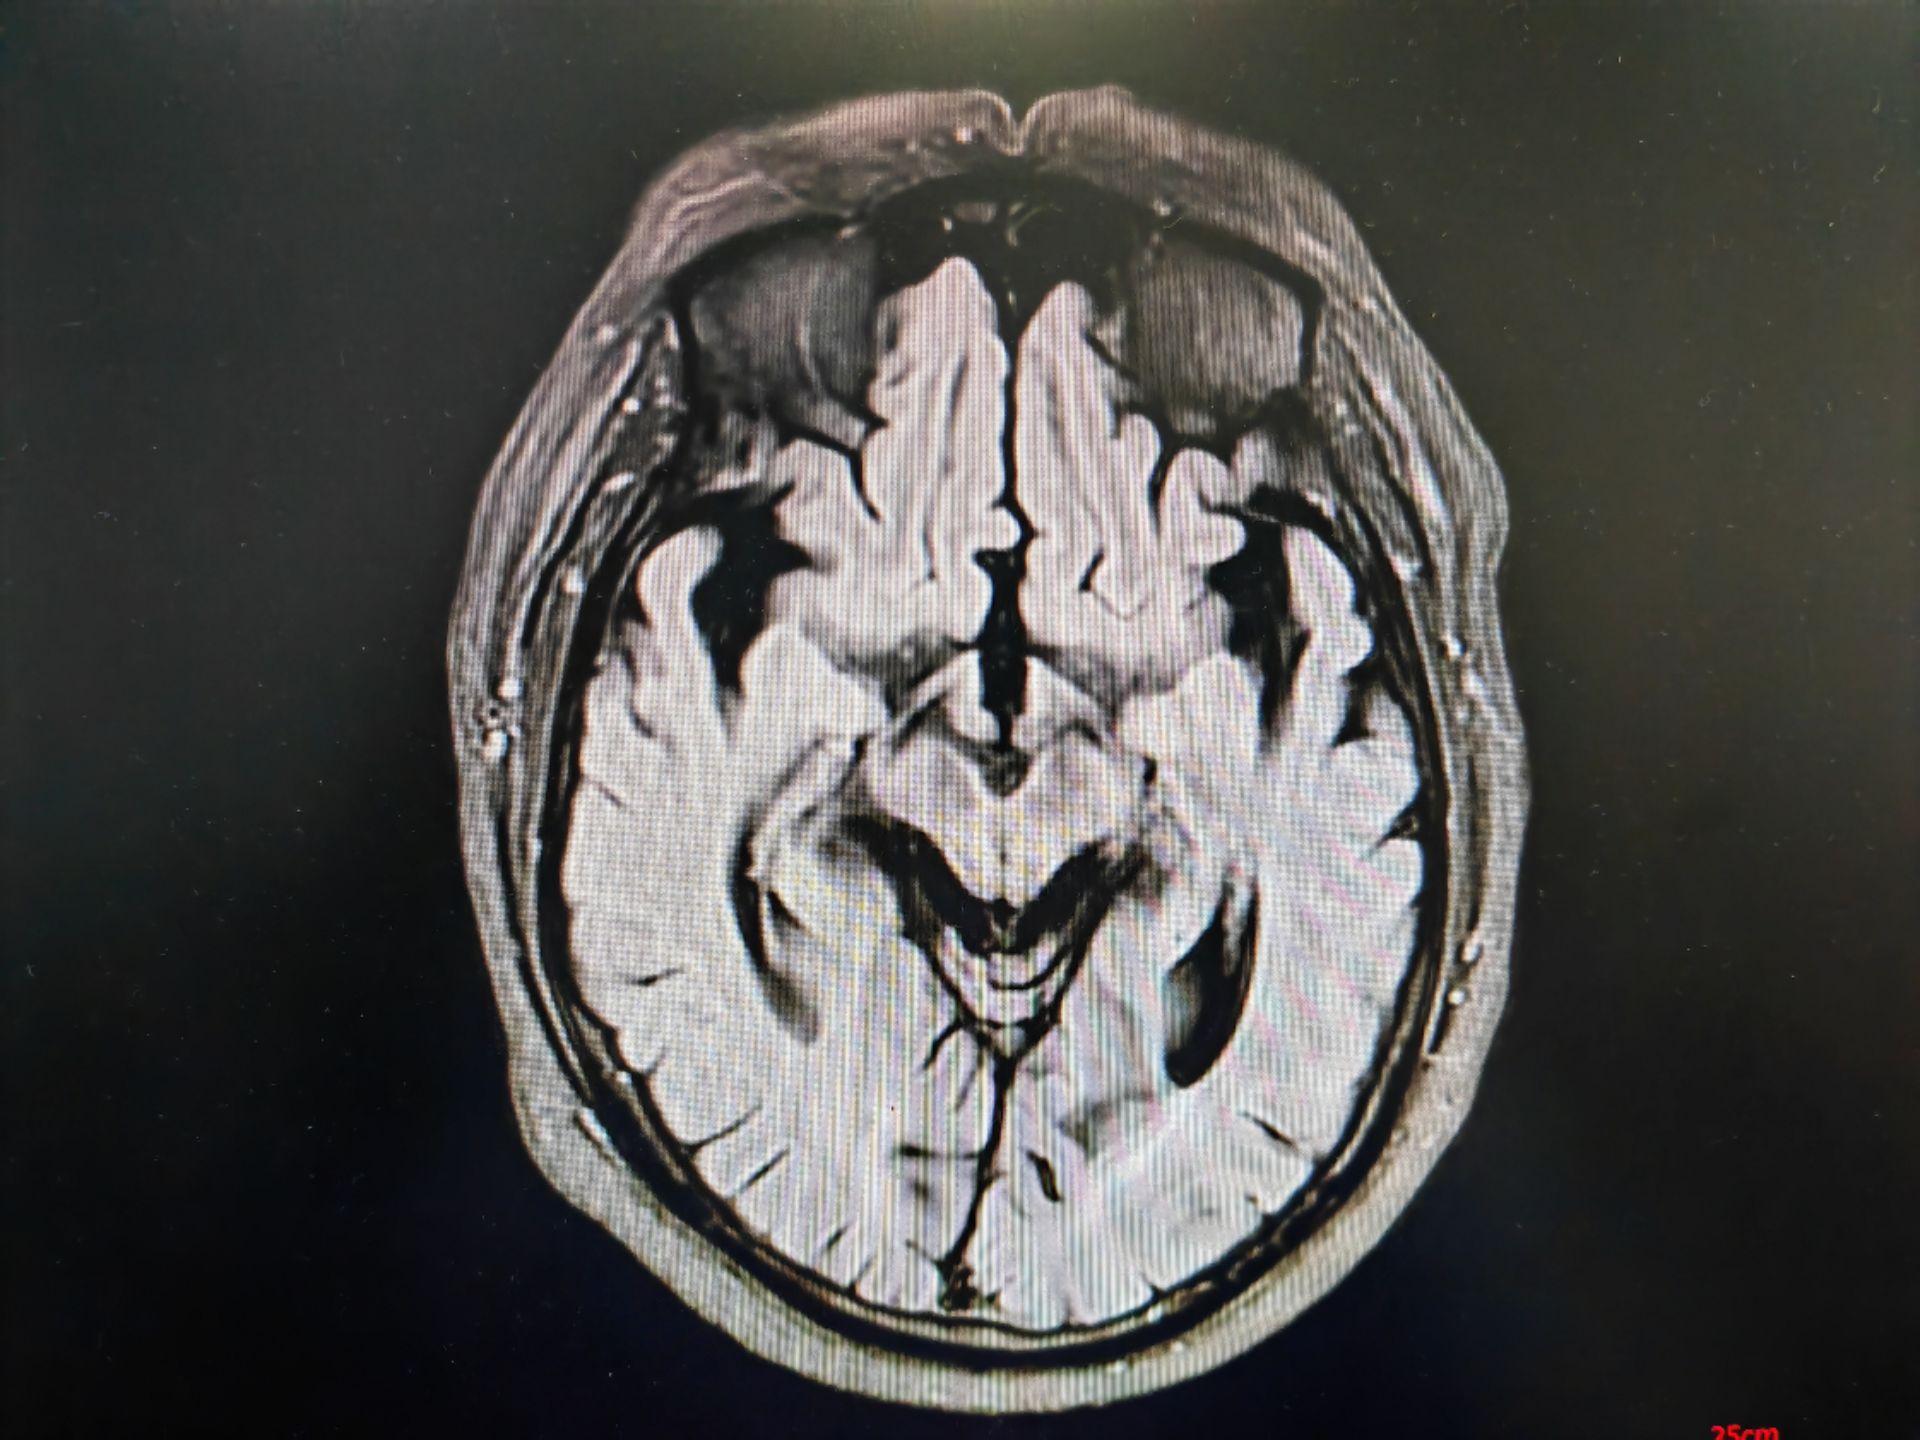

蜂鸟征,米老鼠征,牵牛花征。蜂鸟征 米老鼠征 牵牛花征 进行性核上性麻痹 PSP。PSP 是一种发生于中老年人的中枢神经系统变性疾病,临床表现为轴性强直,垂直性眼球运动障碍, 早期出现反复向后跌倒。但临床诊断为很可能 PSP 患者,经病理诊断证实的阳性预测率约 80%~90%。其临床病理特征为:中脑顶盖和被盖萎缩、黑质色素脱失,第三、四脑室及导水管轻度扩张。